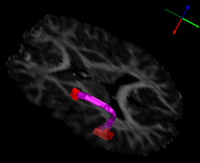

Volumetric Segmentation of the Arcuate Fasciculus

UtahArcuateFasciculusFeb10.png

Microstructural Connectivity of the Arcuate Fasciculus in Adolescents with High-functioning Autism Read more...